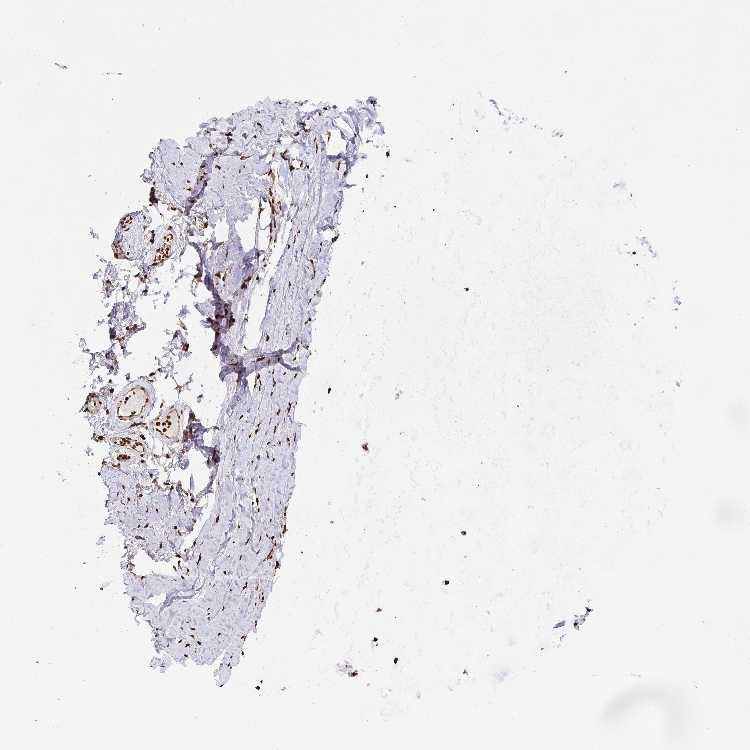

SOFT TISSUE 1 - Antibody stainingi

Antibody staining in the annotated cell types in the current human tissue is reported as not detected, low, medium, or high, based on conventional immunohistochemistry profiling in selected tissues. This score is based on the combination of the staining intensity and fraction of stained cells.

Each image is clickable and will lead to virtual microscopy that enables deeper exploration of all samples and also displays staining intensity scores, fraction scores and subcellular localization as well as patient and tissue information for each sample.

Antibody HPA059387

Chondrocytes High

Fibroblasts High

SOFT TISSUE 2 - Antibody stainingi

Peripheral nerve High